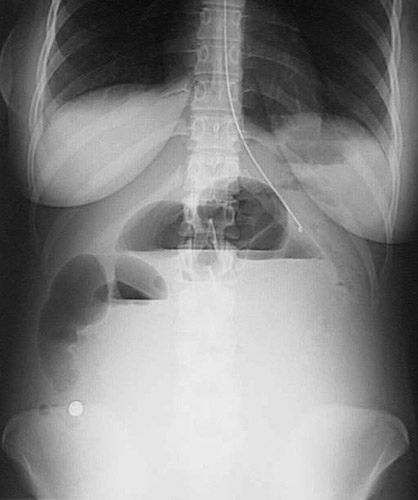

This abdominal radiograph demonstrates contrast material layering in the loops of bowel as a consequence of bowel obstruction with intussusception resulting in lack of peristalsis. A long intestinal tube is visible.